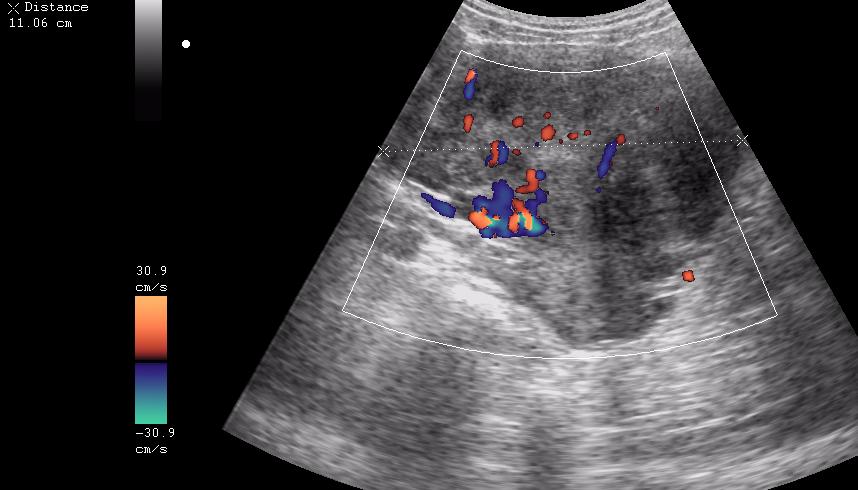

ну вот куда здесь ставить бодимаркер и какой?

ещё раз - это матка 23-летней девушки. то есть, ВСЁ это, то что Вы видите, да-да, на весь экран - это матка.

Диагноз - фиброматоз. направлена строго на север и налево. к соседям. (онкодиспансер)